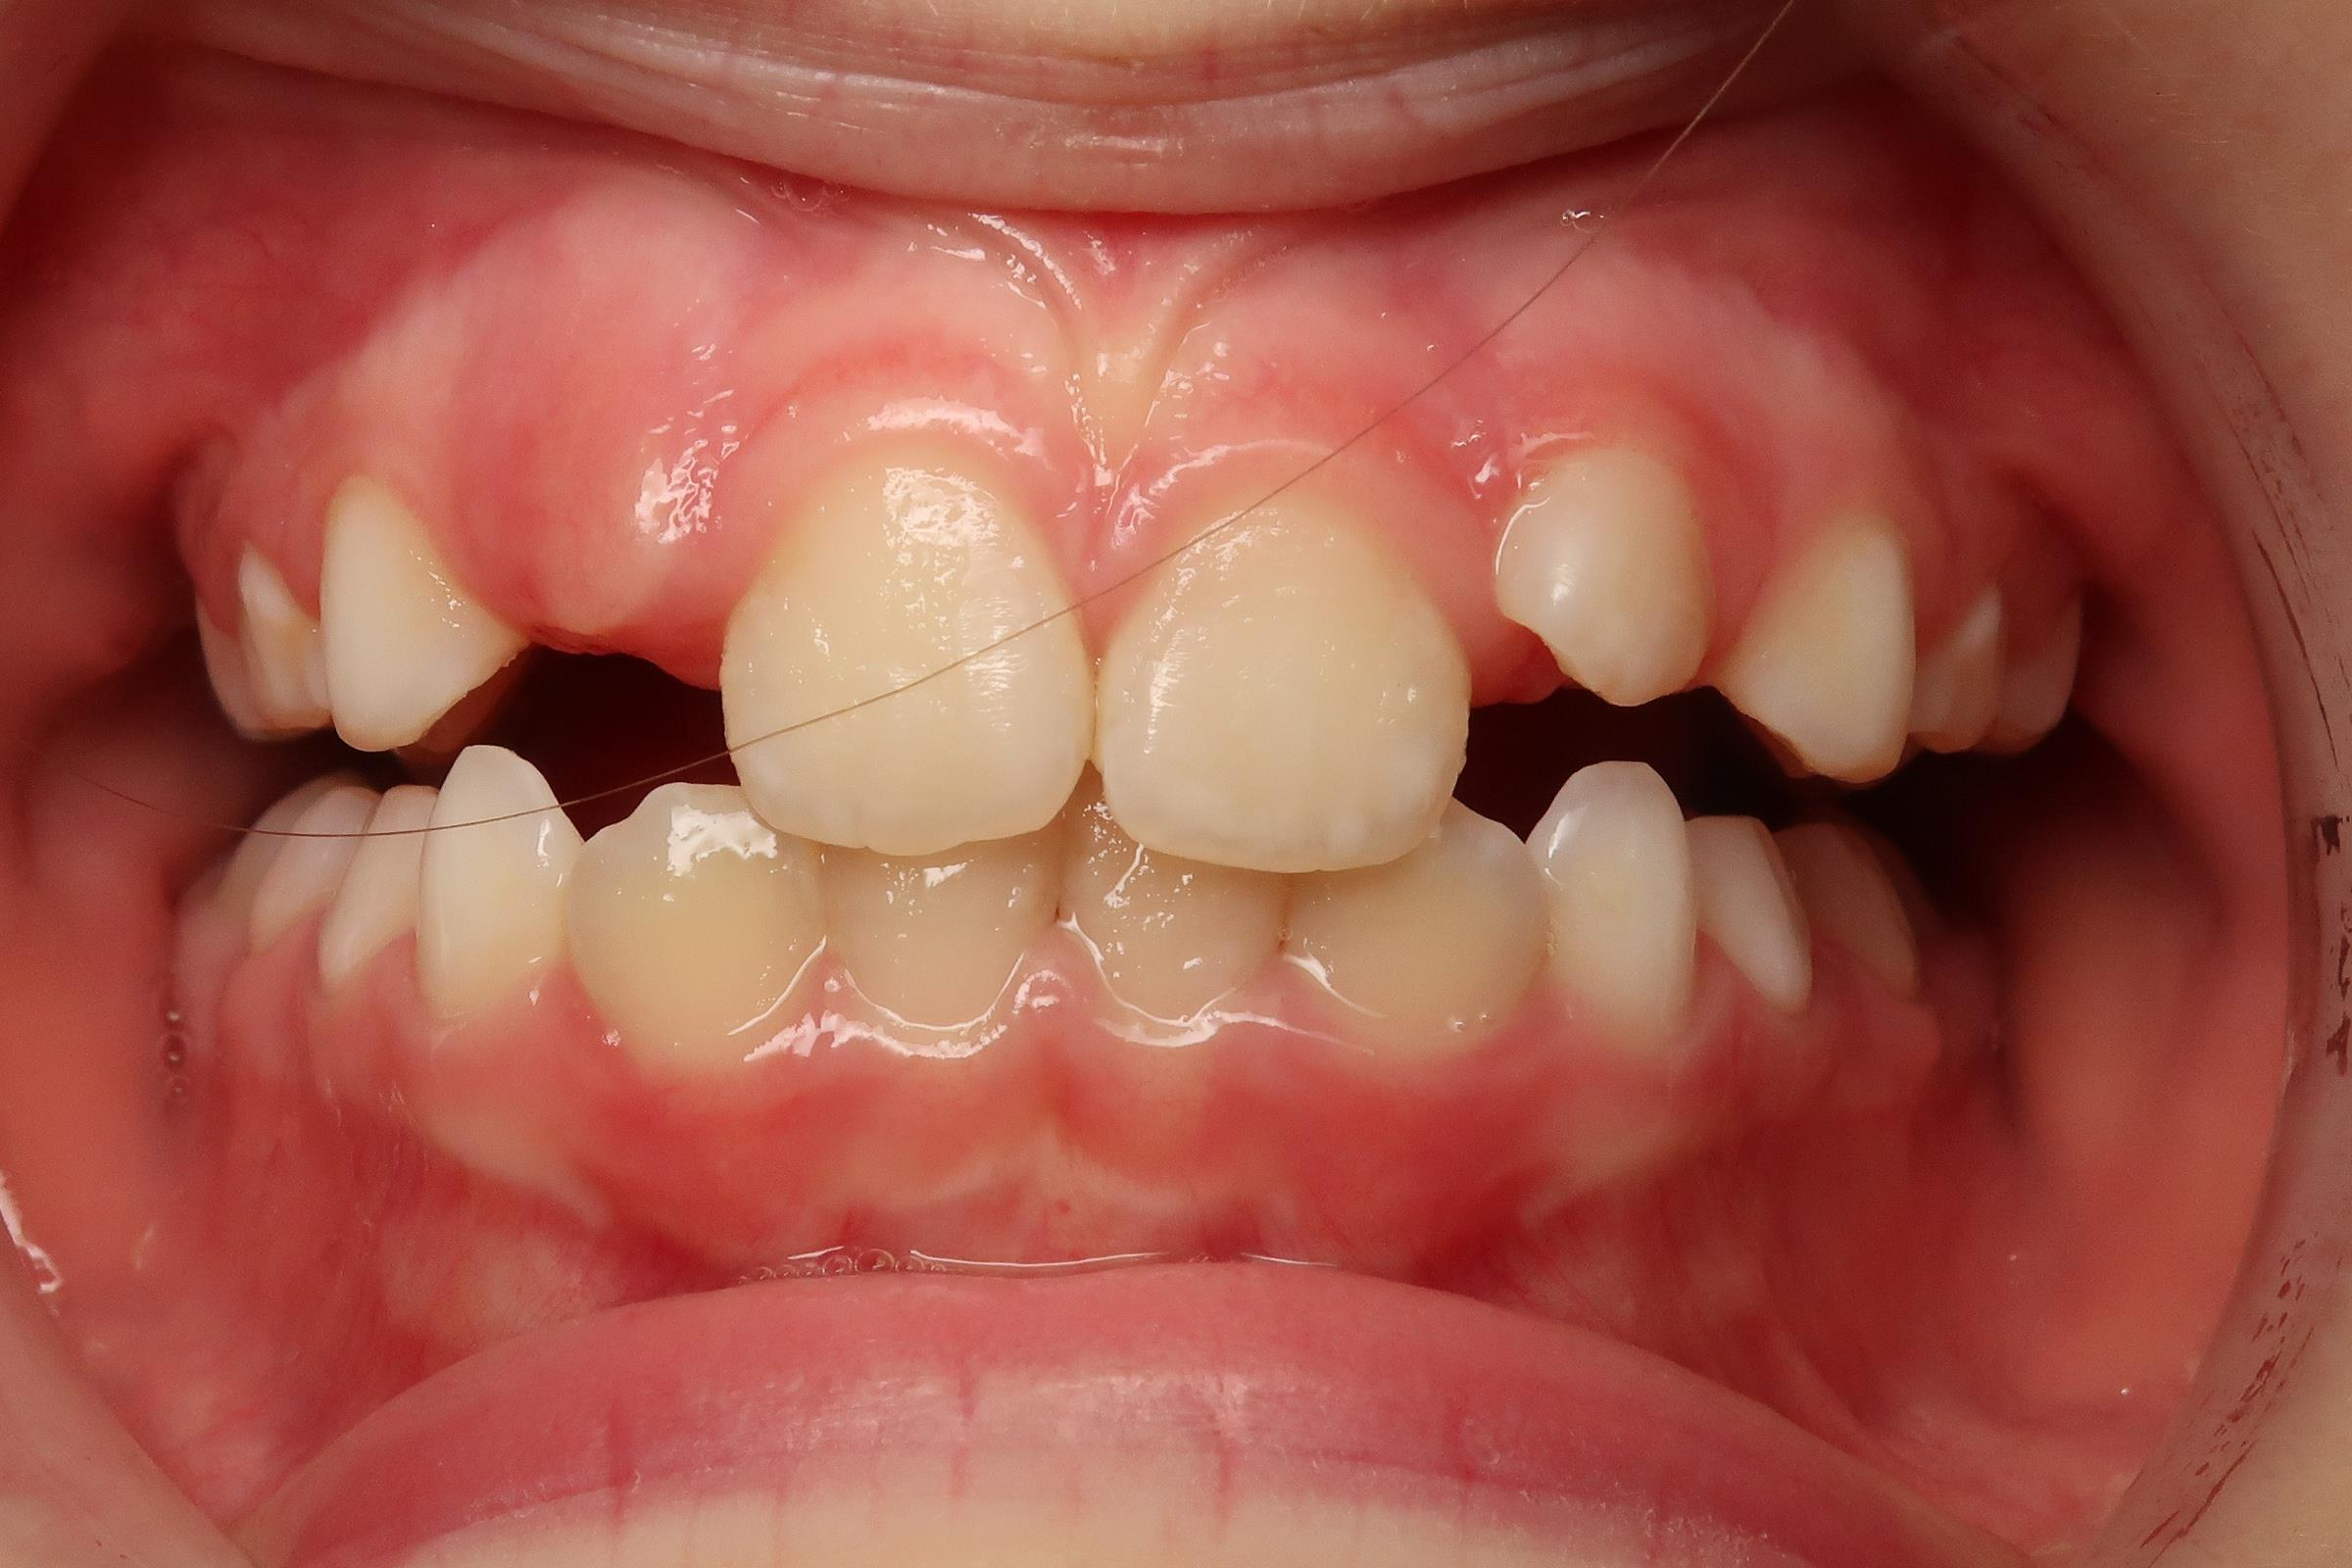

7.inversé droit 4 ans

bilan début et en cours de traitement